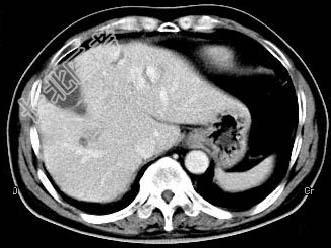

- 单项选择题根据所提供的图像,最可能的诊断是 ( )

A、肝内多发血管瘤

B、肝多发血管瘤并肝癌

C、多发肝囊肿

D、胆管细胞癌

E、以上都不是